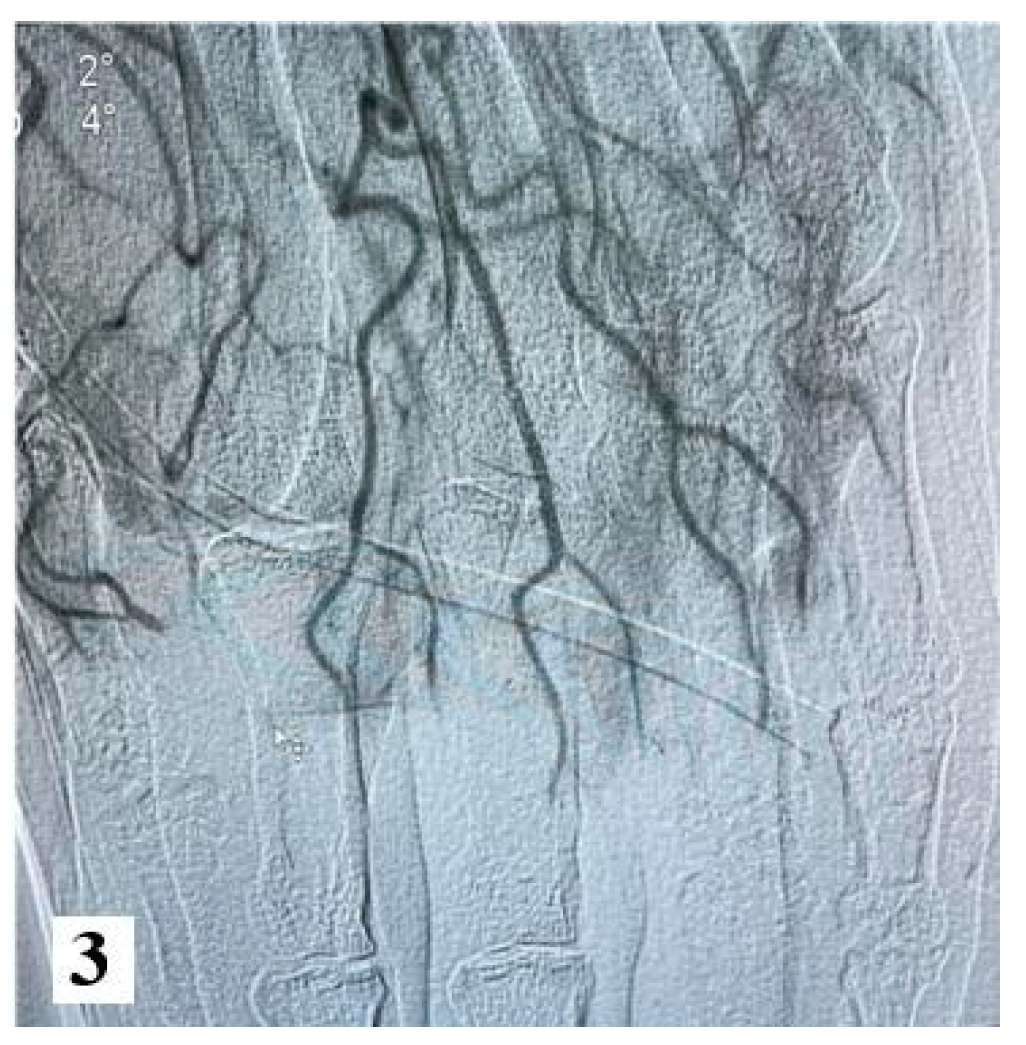

Furthermore, an angiography of the upper limb indicated the absence of vascularization at the level of bilateral proximal phalanges. The brachial, radial, and ulnar arteries were found to be patent, exhibiting a normal appearance.

Figure 3.

Angiography images (from hospital archive) (part 2).